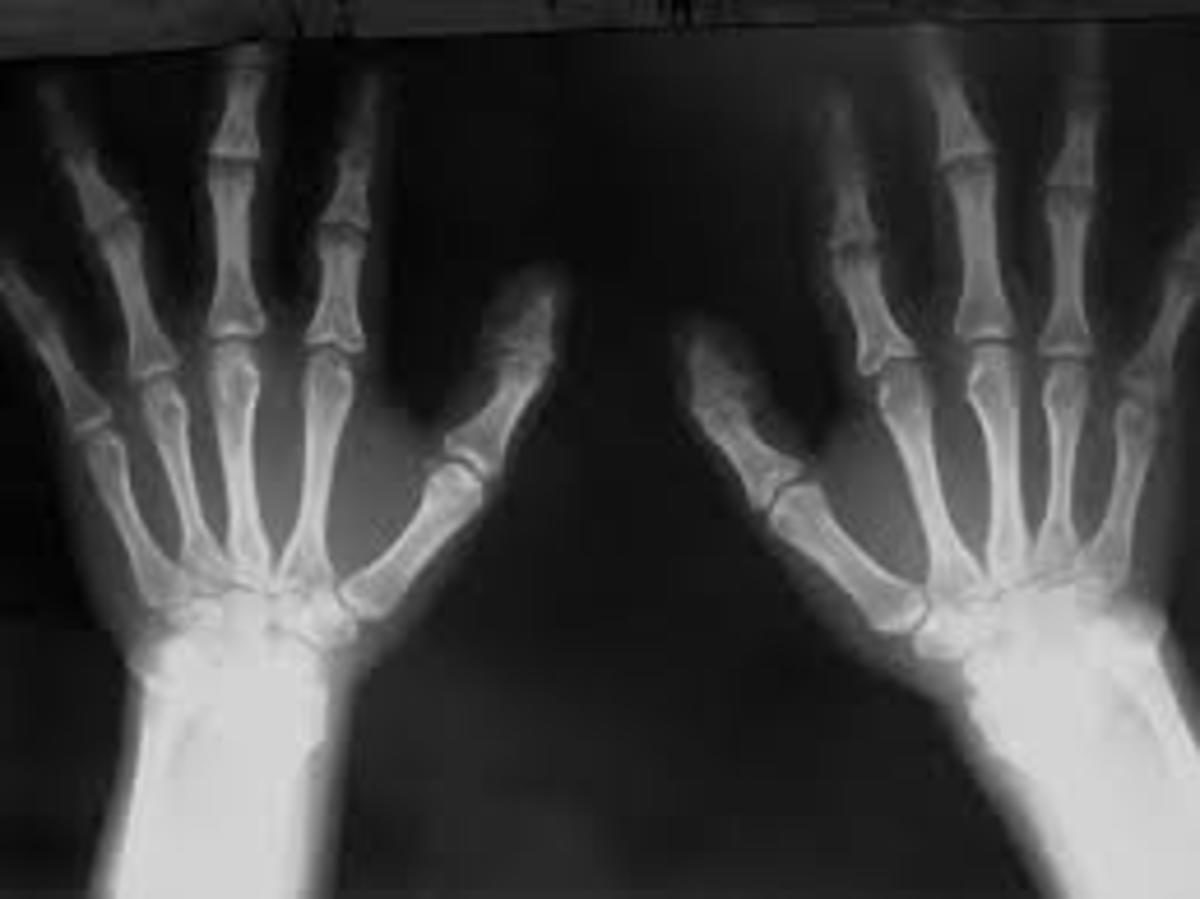

πρήξιμο των αρθρώσεων με πόνο και δυσκαμψία